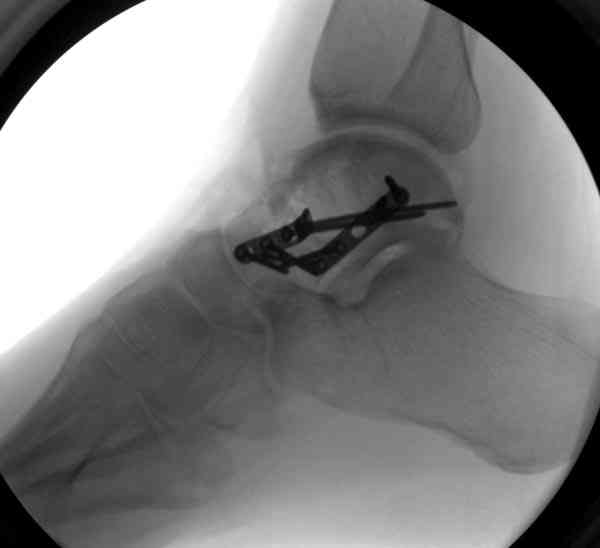

Случай с множественным оскольчатым переломом тарана оперированный из двойного доступа.

Через 8 мес.: